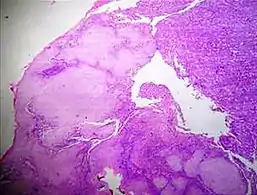

Staining artifacts by residual wax, resulting in pale areas where cellular structures are not discernible..jpg.webp) A separation artifact in top image makes the tumor look incompletely excised, but the next microtomy level (bottom image) shows a surgical margin of connective tissue.

A separation artifact in top image makes the tumor look incompletely excised, but the next microtomy level (bottom image) shows a surgical margin of connective tissue. Stacking of cells on top of each other gives a dark look, and in this breast tissue it may mimic microcalcifications.